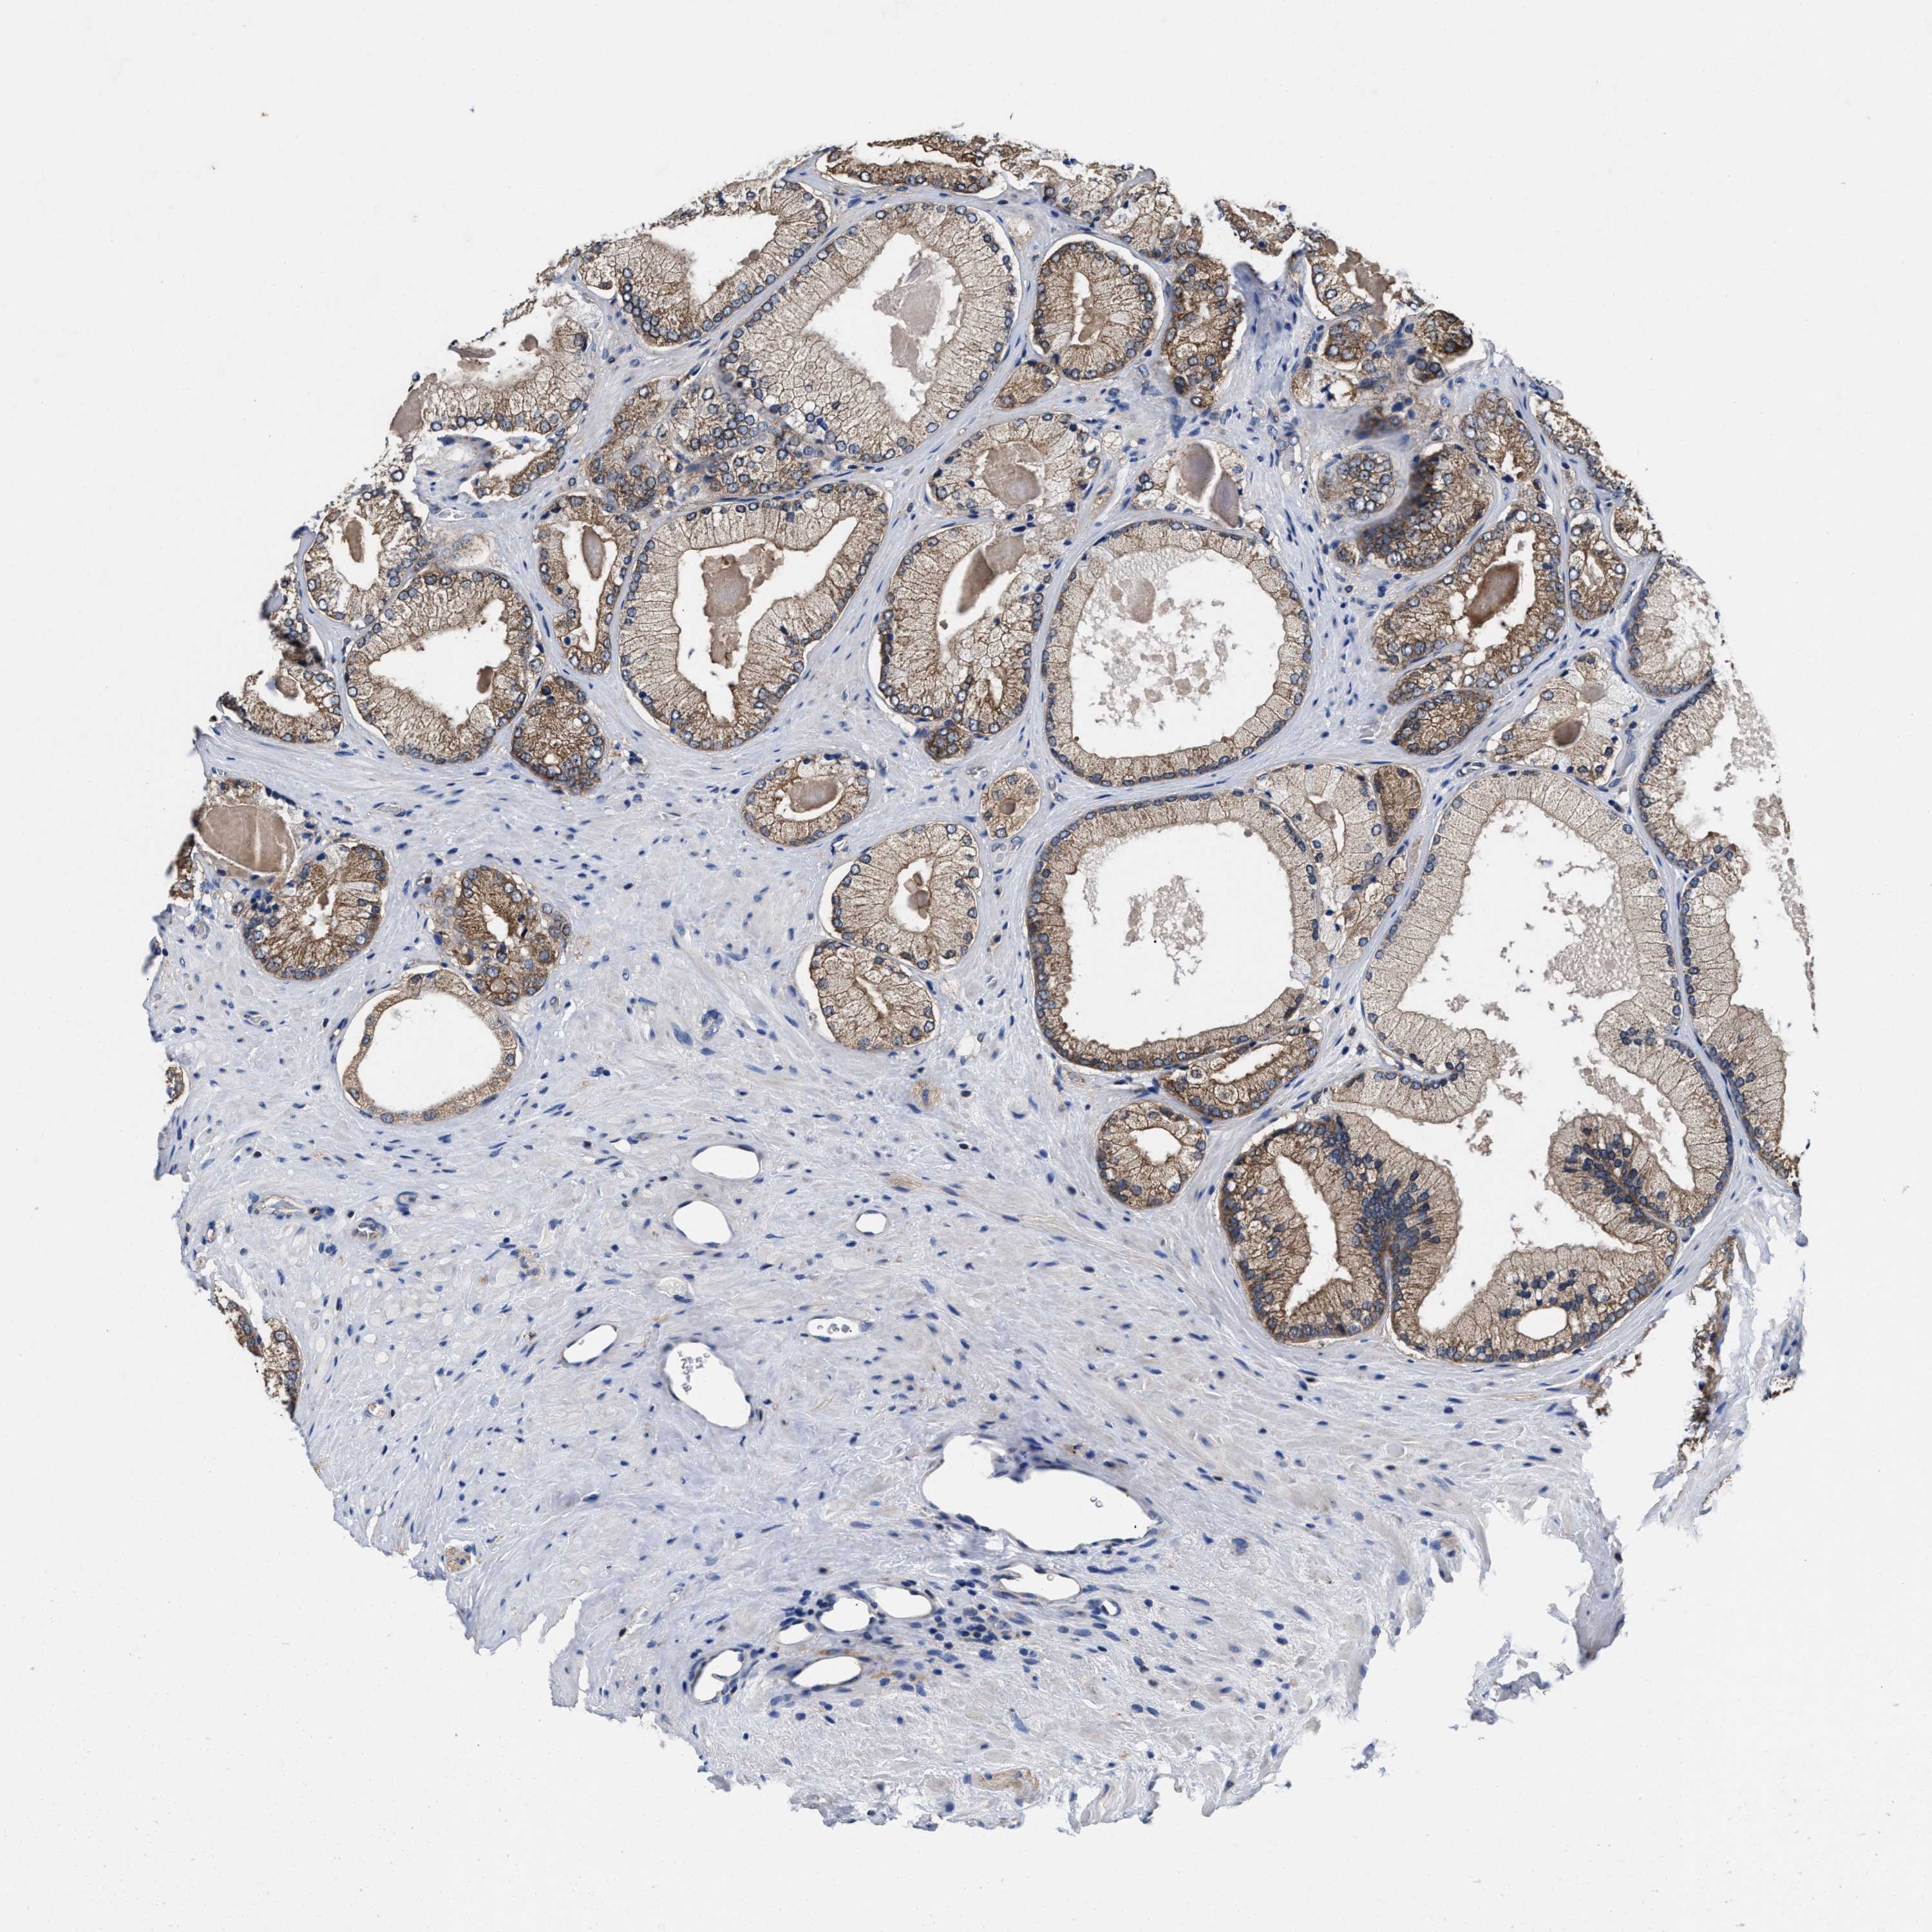

PROSTATE CANCER - Protein expressioni

A mouse-over function shows sample information and annotation data. Click on an image to view it in a full screen mode. Samples can be filtered based on level of antibody staining by selecting one or several of the following categories: high, medium, low and not detected. The assay and annotation is described here.

Note that samples used for immunohistochemistry by the Human Protein Atlas do not correspond to samples in the TCGA dataset.

Antibody stainingi

Antibody staining in the annotated cell types in the current human tissue is reported as not detected, low, medium, or high, based on conventional immunohistochemistry profiling in selected tissues. This score is based on the combination of the staining intensity and fraction of stained cells.

Each image is clickable and will lead to virtual microscopy that enables deeper exploration of all samples and also displays staining intensity scores, fraction scores and subcellular localization as well as patient and tissue information for each sample.

HPA022434

HPA022953

HPA022959

HPA028758

CAB007783

Adenocarcinoma, High grade

Adenocarcinoma, Low grade